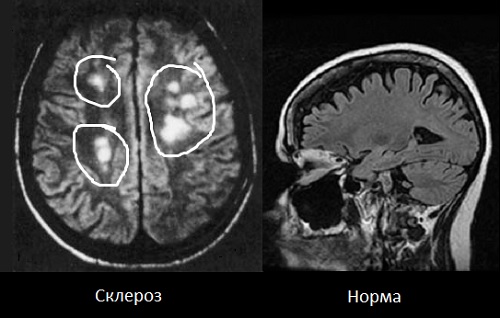

Диагностика рассеянного склероза

Диагностический процесс начинается с внимательного сбора анамнеза и жалоб пациента, а также с проведения детального неврологического обследования.

Для подтверждения диагноза рассеянного склероза необходимо выполнить следующие исследования:

- МРТ (магнитно-резонансная томография) головного и спинного мозга;

Диагноз «рассеянный склероз» ставится неврологом на основе клинических проявлений и жалоб пациента. Специалист проводит обследование, анализируя двигательную функцию и чувствительность. В настоящее время магнитно-резонансная томография (МРТ) считается основным методом для подтверждения рассеянного склероза, так как она позволяет выявить участки демиелинизации.